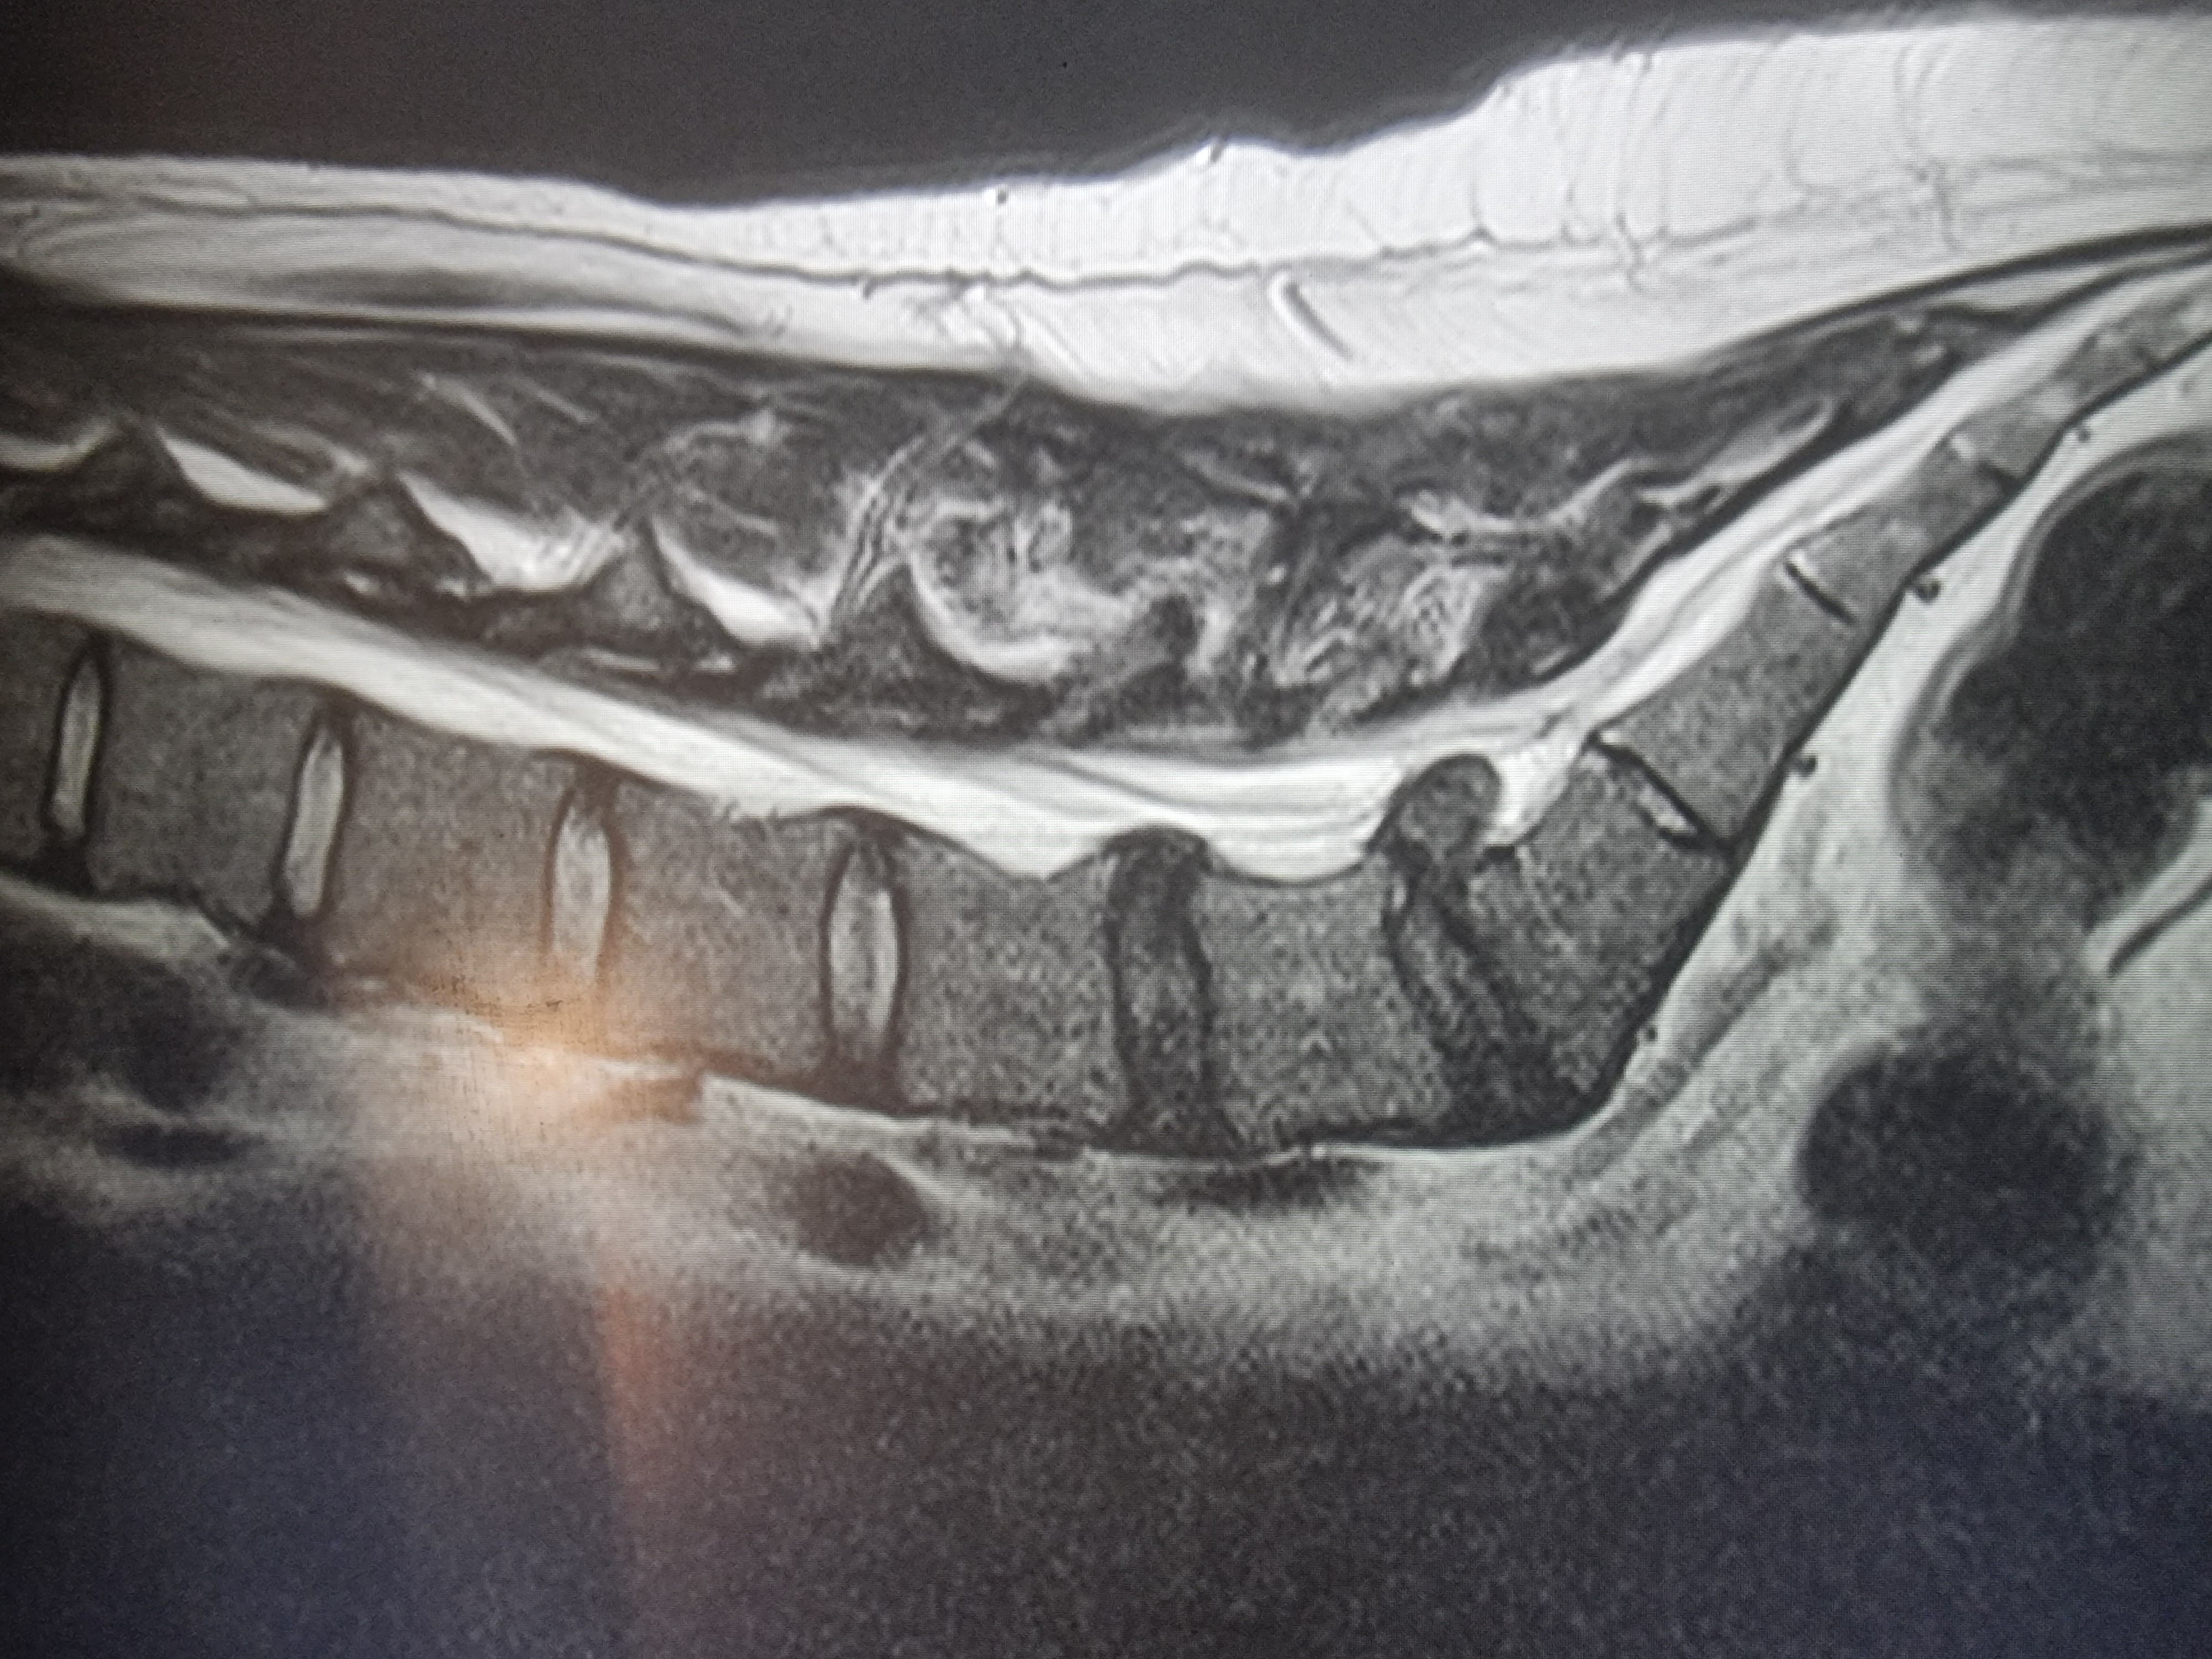

На этой неделе сделал МРТ и... грыжа 12 мм. с разрывом (см. 1 фото). о_О

У тебя экструзия на L5-S1, протрузия L4-L5.